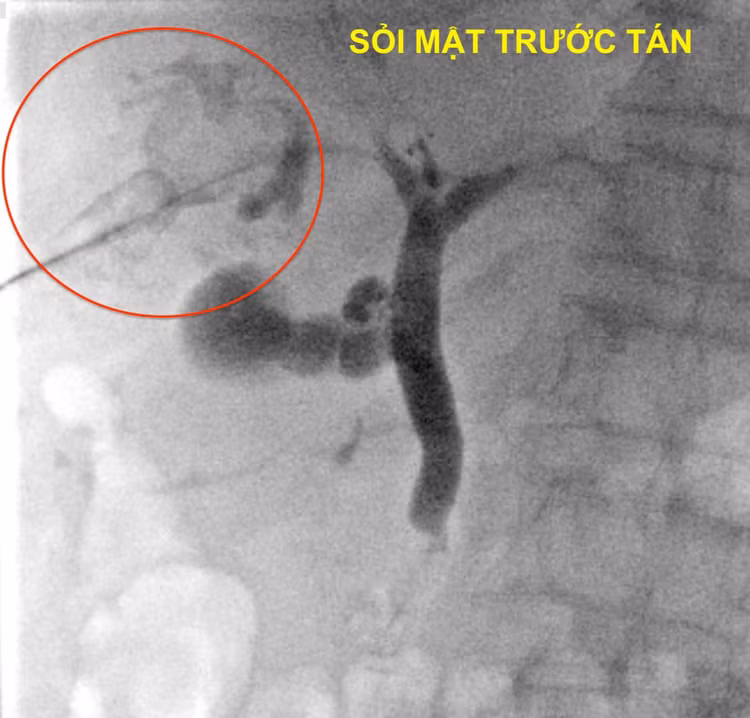

![]() |

| Hình ảnh sỏi mật trước và sau khi tán |